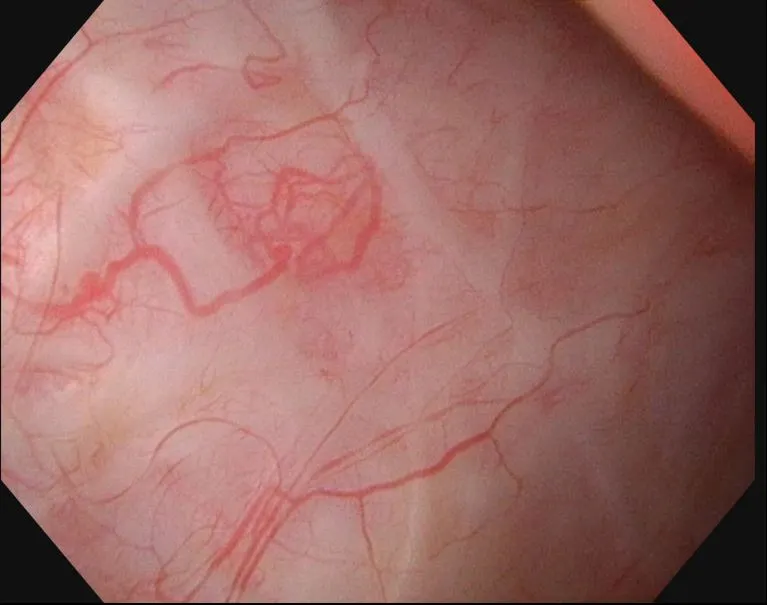

전립선은 방광목 바로 아랫부분에 위치하는 20g 정도, 호두알 크기의 장기이다. 전립선 주변으로는 정자를 저장하는 주머니인 정낭과, 정자의 이동통로인 정관이 위치하고 있는데, 전립선 적출을 시행할 때, 이러한 인접 장기를 모두 제거하고, 방광목과 요도를 다시 이어주게 된다. 때문에, 전립선이 있던 자리에 방사선을 조사하게 되면, 방광의 일부와 요도가 치료 범위에 포함되며, 이로 인해 방광과 요도 점막이 방사선에 의한 변성을 일으키게 되는데, 이 상태에서 혈관이 점막 위로 드러나 파열되면 혈뇨로 이어진다. 항혈전제를 복용하지 않는 경우라면, 대부분은 금방 멈추게 되지만, 약해진 혈관이 반복적으로 파열되면 이 환자와 같이 지독한 혈뇨에 시달리게 된다.

1.JPG 방사선 방광염 환자의 방광벽